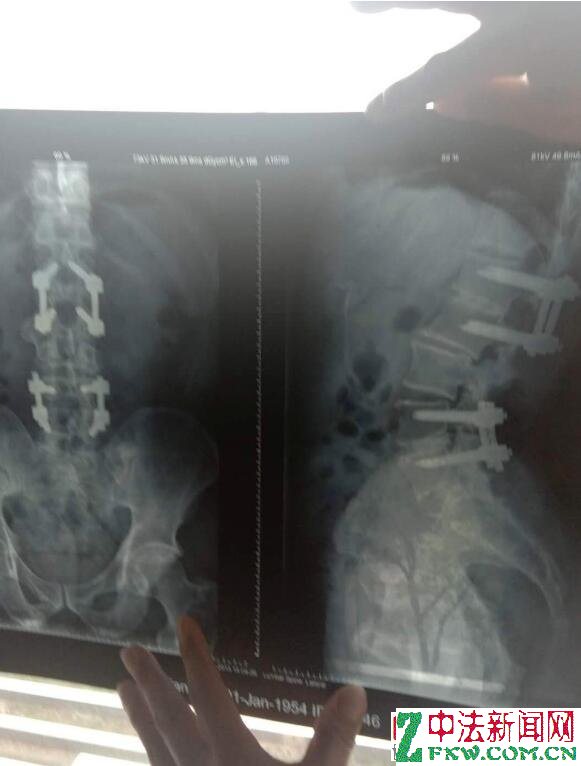

胡尖兵泣诉:2005年1月4号,胡尖兵在永康中医院由杭州117部队某专家给予他行腰椎间盘突出钢钉植入手术。手术中拿掉了他二节腰椎间盘。其中,下一节取错了。腰里植入八根钢钉,二十多根铁螺帽。却把他的腰5-骶1椎间盘突出症,给开到上节腰4-5节了,开到了腰的上一节好的腰椎间盘去了。钢钉压迫留置的下一节坏死的腰键间盘,导致神经受压迫,脚痛麻木更甚,双脚像铁丝网捆住一样,术后造成严重后遗症。腰部肌肉逐渐萎缩僵硬,无法弯腰,18年了都无法弯腰穿袜子,捡东西。经过多个省级骨科专家诊断,术后造成腰部肌肉完全萎缩僵硬。

现在,胡尖兵多处腰椎间盘重新突出,蛛网膜下腔神经根压迫等等,后遗症非常严重。只能拄着拐杖在街上挣扎游走,十五年来去过上海、杭州浙一、杭州117部队医院骨科、金华中心医院、永康人民医院中医院等地。多个骨科博导,主任医生、专家均说无治疗恢复效果了,上述都有详细的医疗证明。开刀前做了四个CT,四个核磁共振,一个椎管造影,一个腰椎平片 。